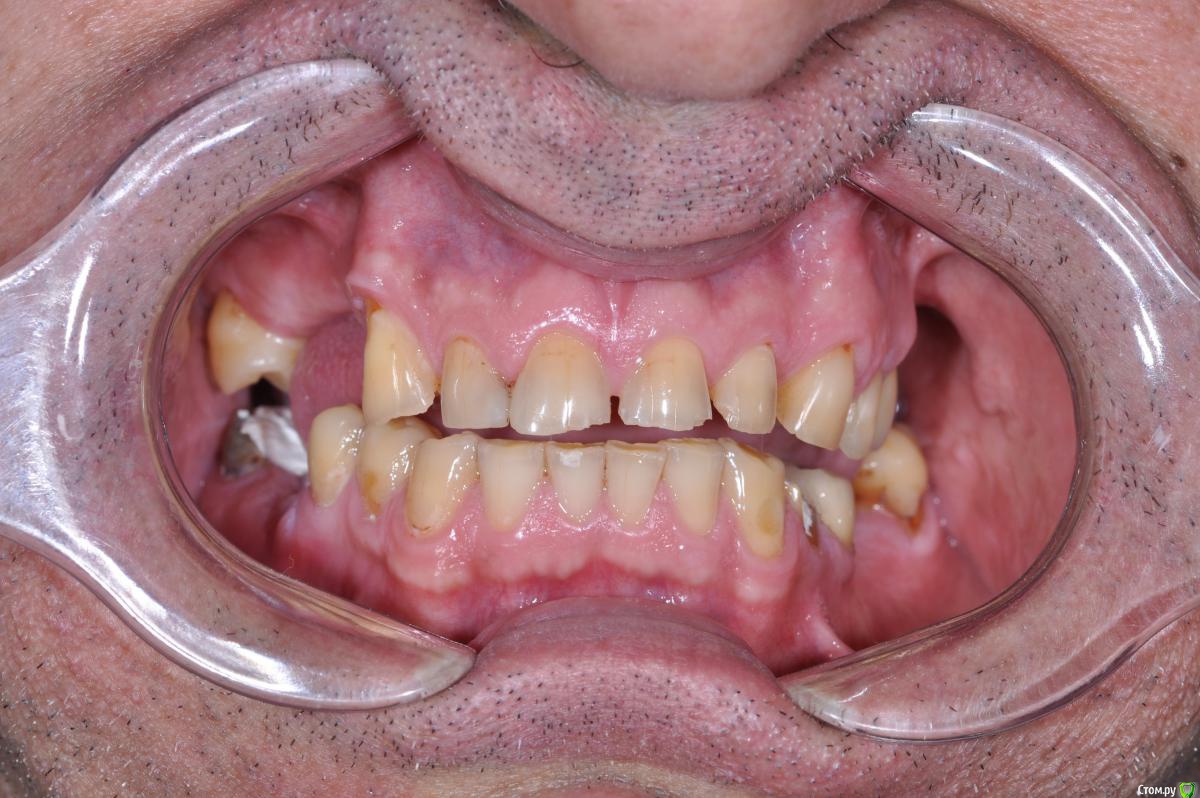

Neilrus Опубликовано 24 января, 2019 Поделиться Опубликовано 24 января, 2019 Здравствуйте, коллеги. Вопрос по выбору типа реставрации, есть пациент с полностью несъемным низом, а вот на верхней челюсти посмотрите на фото и снимок, пожалуйста, 17зуб, потом 13-25. Имлантация на верхней челюсти в ближайшие годы не предвидится по ряду причин. отработали пациента на капах, утвердили мокап, скоро начнем. Стираемость изнутри восстановлю композитом и обработаю под коронки. Вопрос по типу коронок, хочется и красиво и надежно.Верх: Понятно что если иметь ввиду что это мужик с такой объемной потерей тканей, да еще со съемником, то центр желательно цирконий, может даже преттау, но адгезия плохая пугает, да и внешний вид даже с хорошим техником не очень.Дисиликат с нанесением? Как вы считаете, выдержит?Гипертонуса нет, не бруксист, будет каппа ночная на низ, конечно Низ: Тут выбор между коронками и винирами (не на огнеупоре ,а обычные)жевательные низ пока временные, потом выведу их по плоскости, там emax без нанесения будут и цирконий на импл. Как бы поступили вы? Ссылка на комментарий

kramer Опубликовано 24 января, 2019 Поделиться Опубликовано 24 января, 2019 Мне кажется тут все признаки бруксизма 1 Ссылка на комментарий

Neilrus Опубликовано 24 января, 2019 Автор Поделиться Опубликовано 24 января, 2019 Мне кажется тут все признаки бруксизмасейчас нет уже Ссылка на комментарий